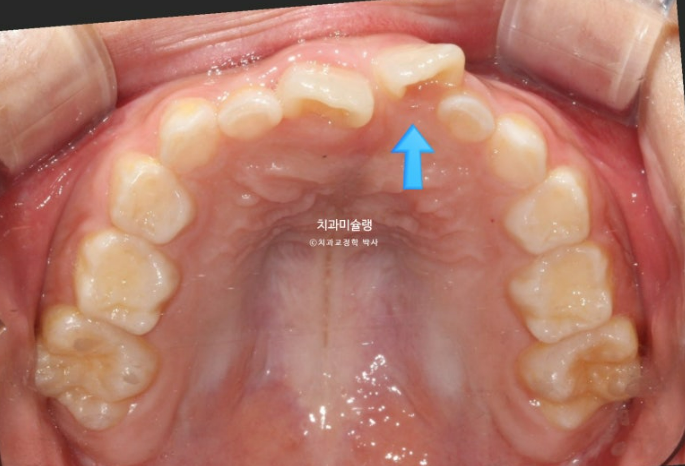

앞니가 거꾸로 물려서 온 7세 어린이 입니다.

윗니가 전체적으로 아랫니와 거꾸로 물리는 반대교합 입니다.

공간부족으로 앞니가 덧니처럼 나왔습니다.

엑스레이 골격분석 결과 뼈의 주걱턱은 아니였어서 프리올소 치료를 권유드렷고